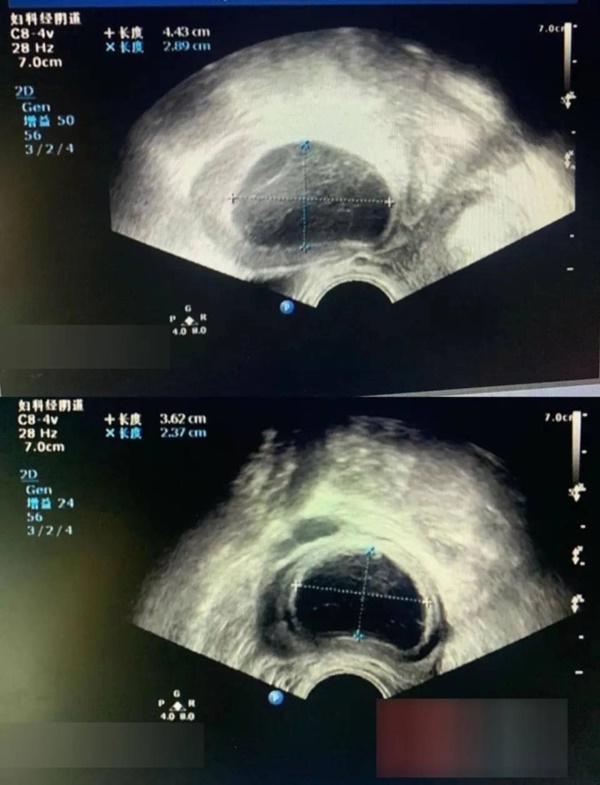

Sau khi nhập viện, bác sĩ Trưởng khoa Phụ khoa Diệp Vũ Tề đã loại trừ khả năng cô Trương có thai ngoài tử cung. Qua siêu âm màu, trưởng khoa Diệp phát hiện buồng trứng trái của bệnh nhân xuất hiện những dấu hiệu bất thường và khoang chậu có chất lỏng. Cuối cùng, bác sĩ đưa ra chẩn đoán cô Trương bị vỡ buồng trứng.